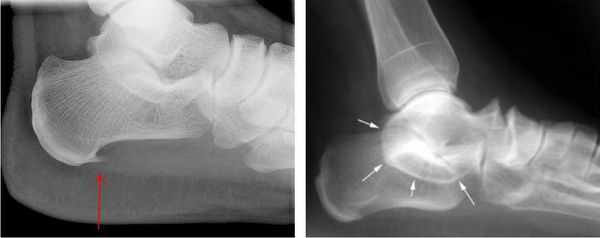

При этом, рентгенографические исследования (МРТ, КТ, УЗИ) стопных отделов под нагрузкой, позволяют выявить наличие/отсутствие различных деформационных изменений, остеофитов, переломов, а также иных видов проблем, провоцирующих изменение нормальной формы канала предплюсны.

Как правило, рентген помогает специалисту получить оптимально корректную информацию и, на ее основе, применить наиболее эффективную тактику лечения - консервативную, либо хирургическую.

При подозрении травматической природы синдрома проводится рентгенография голеностопного сустава и стопы. Во время исследования также можно обнаружить костные выступы и остеофиты.

Для выявления патологий мягких тканей проводят МРТ голеностопного сустава стопы: могут быть обнаружены тендинит (дистрофия сухожилия), теносиновит (воспаление сухожилия), липомы или другие новообразования, варикозное расширение вен и кисты ганглиев.